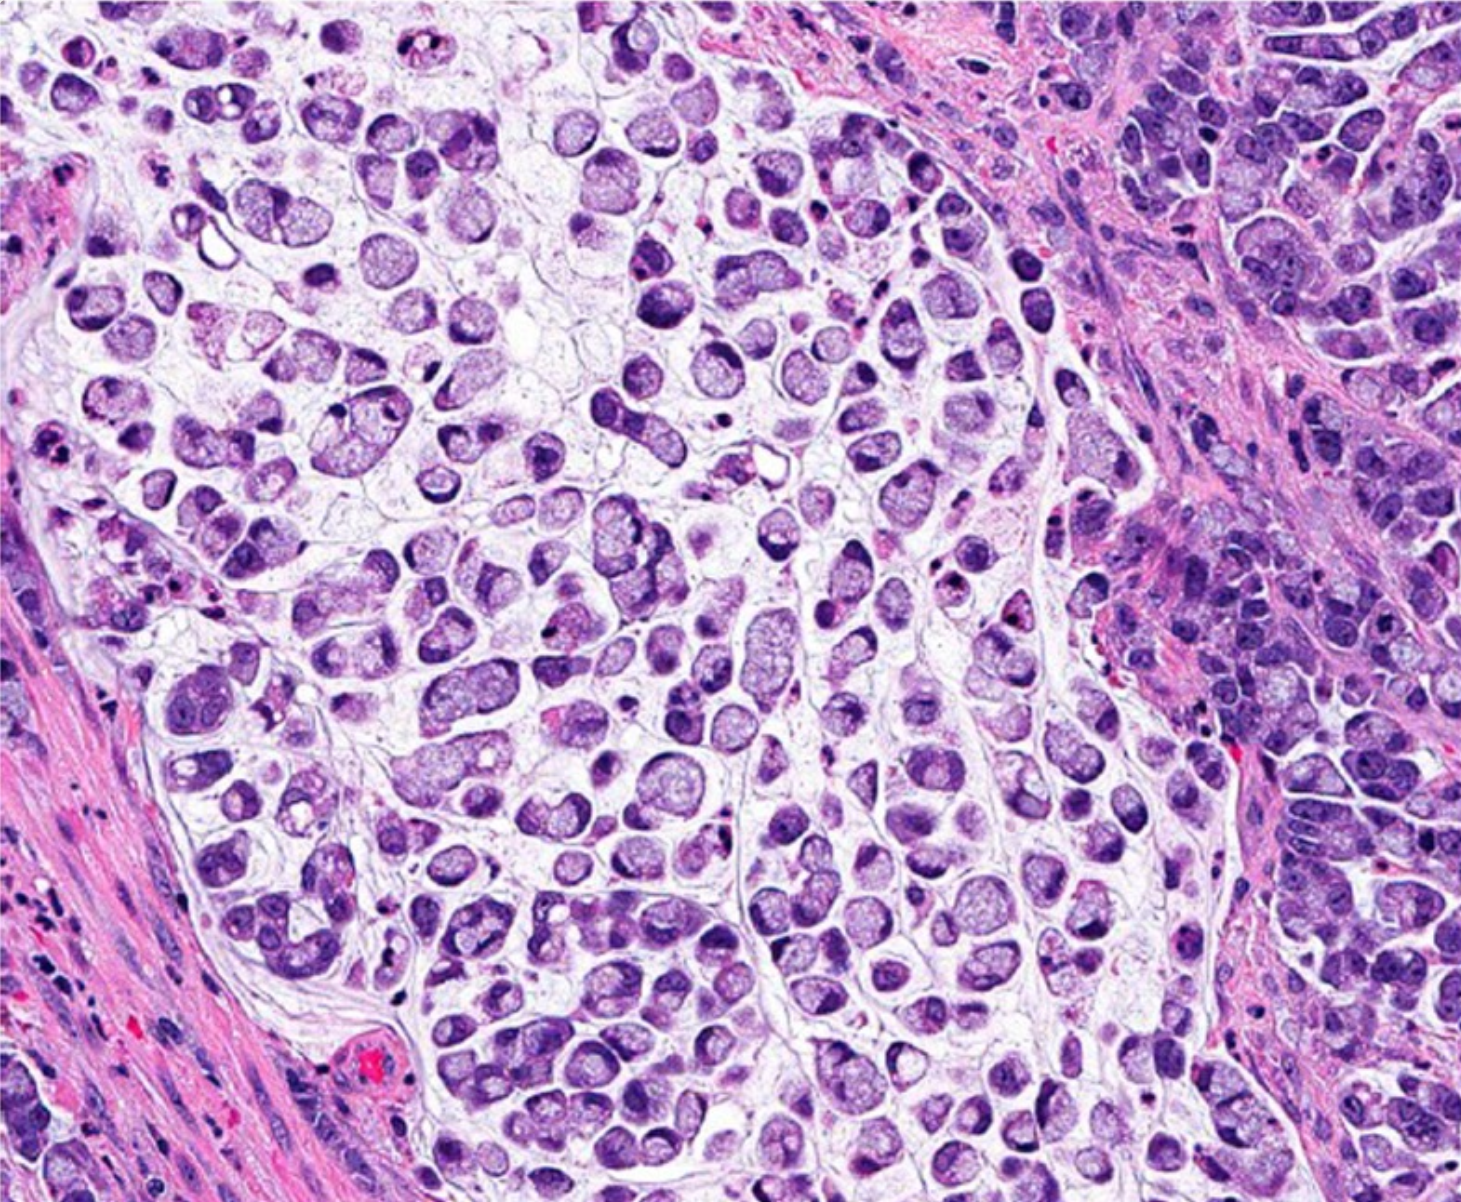

超过90%的结直肠癌是起源于结直肠粘膜上皮细胞的腺癌(adenocarcinoma)。 其他罕见类型的结直肠癌包括神经内分泌细胞癌(neuroendocrine)、鳞状细胞癌(squamous cell)、腺鳞状细胞癌(adenosquamous)、梭形细胞癌(spindle cell)和未分化癌。 常规腺癌以腺状结构为特征,这是肿瘤组织学分级的基础。在高分化腺癌>中,95%的肿瘤是腺形成的。 中分化腺癌显示50-95%的腺体形成。低分化腺癌多为实性,腺体形成率小于50%。 在实践中,大多数结直肠腺癌(约70%)被诊断为中分化(图2)。高分化癌和低分化癌分别占10%和20% [4]。下面将主要介绍几种腺癌的类型。

若本图无法展示,请更换浏览器查看

图2.中等分化腺癌例,在间质间质中可见复杂的腺体结构(放大原图×200) [4]。